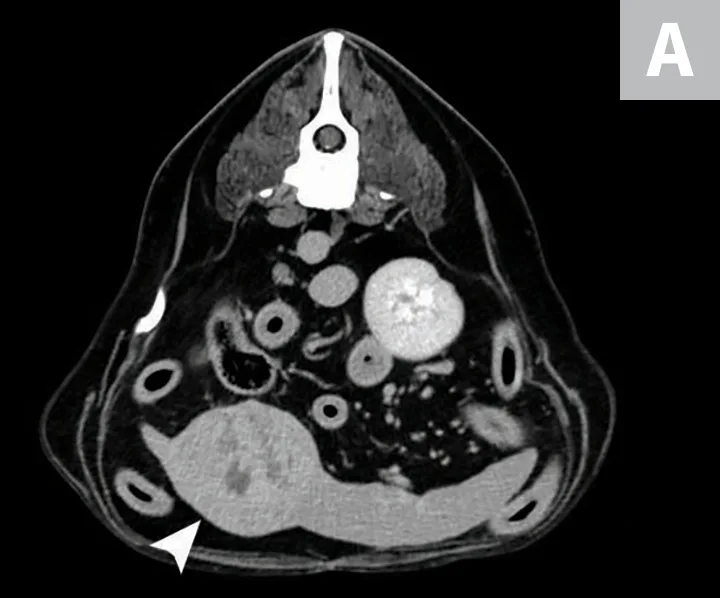

Although HSA can be presumptively diagnosed based on multiple clinical and physical findings and patient signalment, baseline diagnostic tests (see Baseline Diagnostic Tests) should be considered in patients that have probable HSA. Detailed images of HSA lesions arising from visceral organs, SC tissue, and deeper muscle structures can be acquired with advanced imaging modalities (eg, CT; Figure 3).

CT images of primary splenic HSA (A, arrowhead), SC HSA (B, arrowhead), and deep-muscle HSA (C, arrowhead). Figures courtesy of Louis-Philippe de Lorimier, DVM, DACVIM (Oncology)